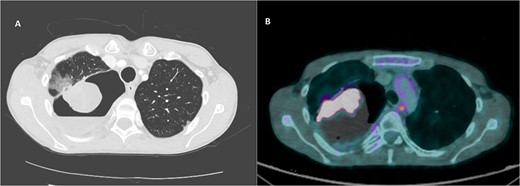

CT imaging of right intracavitary lung mass found within the wall of a longstanding bulla, along with heterogeneous fluid layering within the cavity (A). The mass was reported to be 4.4 × 5.2 cm and was concerning for primary bronchogenic malignancy. This lesion increased to 6.8 × 5.9 cm, demonstrating intense increased FDG activity and interval increase in fluid layering within the bulla within 2 months on follow-up PET imaging (B).

A PET scan done 2 months after the original CT scan showed that the lesion had increased in size (3.3 × 6.8 × 5.9 cm compared to previous CT findings of 2.7 × 3.9 cm), and demonstrated intense increased fludeoxyglucose (FDG) activity, with several smaller foci of similar intense grade FDG avid soft tissue nodules along the posterior aspect of the inferior bulla (Fig. 2). There was also an interval increase in fluid layering within the bulla. There was no distant metastasis.